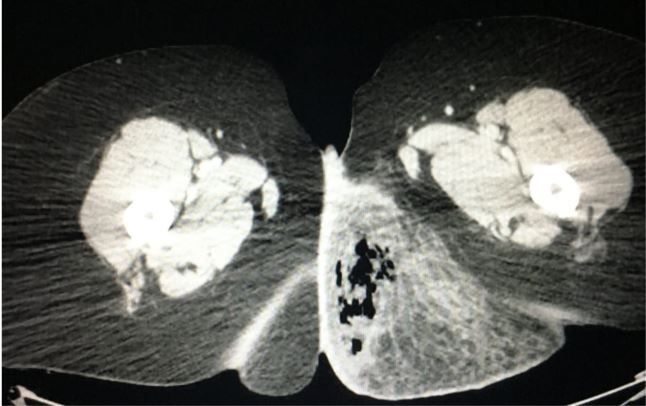

A woman in her forties presents to the ED with 3 days of generalized malaise and worsening pain in the left buttock. What is seen on the CT? Your Dx?

Examination. Vital signs were a bit “soft” with a pulse of 102 beats/min and a BP of 92/51 mm Hg, corresponding to a shock index >1.0 (HR/SBP). Physical examination was otherwise normal except for a red swollen left buttock area.

Due to the soft vitals, bandemia, and elevated lactic acid a CT scan was done (case image below) to see if there was any abscess or other reason for a surgical consult.

Nec-Fasc fromThe Emergency Medicine 1-Minute Consult Pocketbook